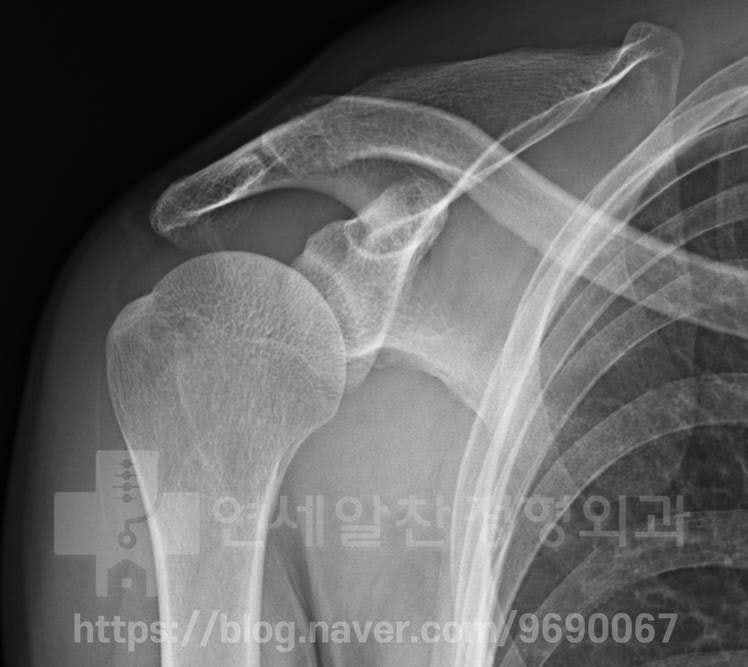

어깨회전근개파열 일 때 부분 파열인 경우 보전적 치료를 하게 됩니다. 부분파열의 크기나 양상에 따라 달라질 수 는 있지만 크기가 크지않고 관절면측 파열이 있는 경우 보전적 치료로 좋은 결과를 보일 수 있습니다. 보전적 치료로는 염증 및 통증을 줄이는 약물, 주사치료가 있으며 인대를 직접적으로 자극하여 치료하는 인대강화주사, 프롤로 치료가 있습니다. 또한 간접적으로 어깨회전근개파열 주변 혈류량을 증가시키고 조직을 자극할 수 있는 체외충격파 치료를 할 수 있습니다. 이외에도 파열된 인대의 부하를 줄이면서 주위 근육 및 인대의 강화 및 기능 회복을 위한 재활도 매우 중요합니다. 환자들이 " 파열이 있으면 보전적 치료로는 치유될 수 없지 않나요?" 하고 질문을 하십니다. 물론 파열의 크기나 양상에 따라 바로 수술적 치료가 필요한 경우가 있습니다. 하지만 보전적 치료로도 충분히 치료될 수 있는 경우가 있으며 이를 잘 감별하여 보전적 치료를 할 지 수술적 치료를 할 지 결정해 주는 것이 환자와 의사 둘 모두에게 시간과 노력을 아낄 수 있다고 생각합니다. 오늘 보여드릴 케이스는 4개월 전 헬스 운동을 하다 통증이 발생되었으며 처음에는 휴식을 하였으나 점점 더 통증이 심해져 타병원을 내원하여 극상근의 파열이 있다는 진단을 받았으며 수술적 치료를 해야 한다고 이야기를 듣고 본원으로 내원한 환자분 입니다. 우선 이학적 검사를 통해 극상근의 문제가 있음을 확인하였기에 (empty can test 양성) 정밀 진단을 위해 X-ray 를 검사하였으며 큰 문제를 발견하지 못했습니다.

X-ray 상에서는 정상 소견이 보입니다. 다음으로 초음파 검사를 통해 문제를 살펴 보았습니다.